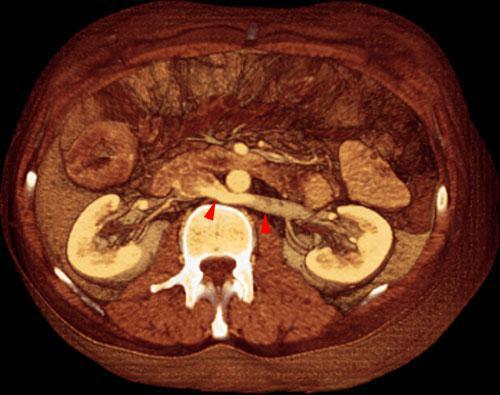

Vena renal izquierda retroaórtica

VR seccional. Visión axial caudal. AngioTC renal visualizándose una vena renal izquierda de situación retroáortica (puntas de flecha)